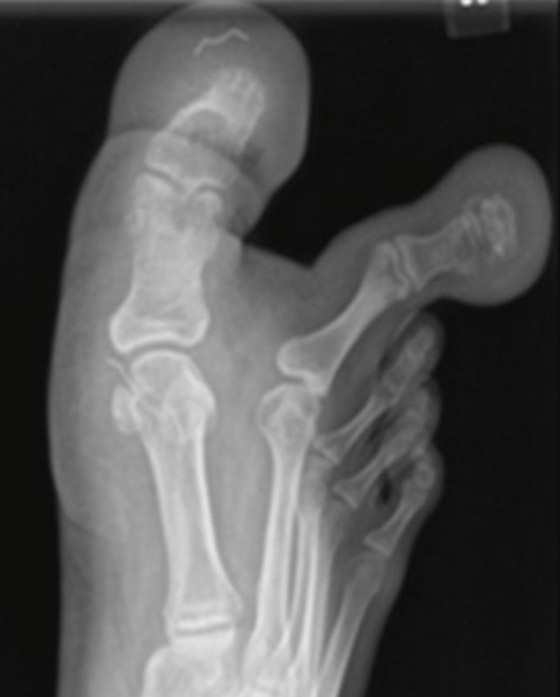

ومن جانبه، قال فريقها الطبي: "كشفت الصور الشعاعية البسيطة ونتائج التصوير بالرنين المغناطيسي عن تراكم الأنسجة الدهنية حول إصبع القدم الأول والثاني، والجوانب الوسطى والجانبية لمشط القدم الأول، وتمتد حتى القوس الأخمصي الأوسط للقدم". وأضاف إن MDL هو نوع غير شائع جدًا من العملقة الخلقية الموضعية، وغالبًا ما يتم إجراء الاستشارة الجراحية لأسباب تجميلية لتعزيز وظيفة القدم والتخفيف من أي مشاكل تتعلق بارتداء الأحذية.